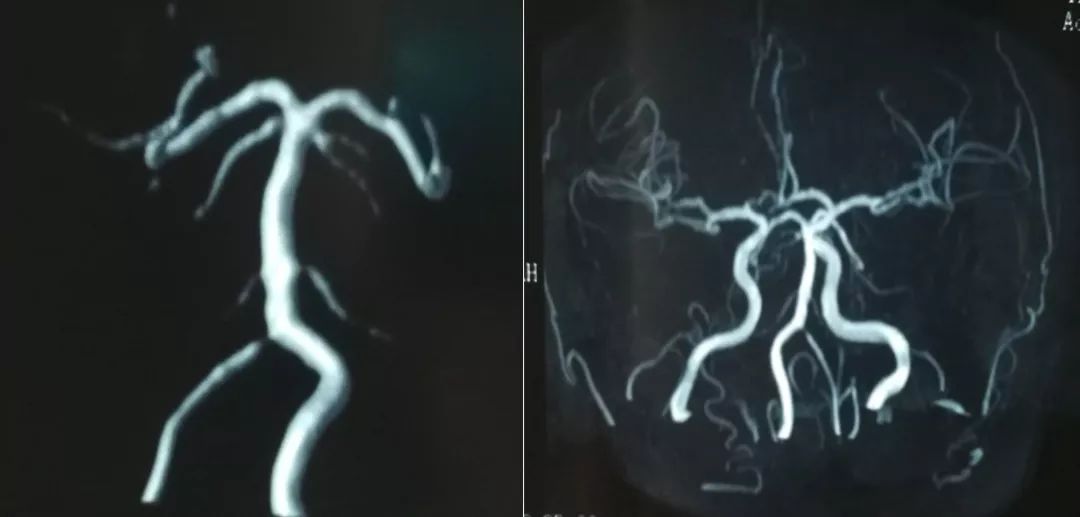

当地医院MRA检查(2019-9-9)(图2)

图2